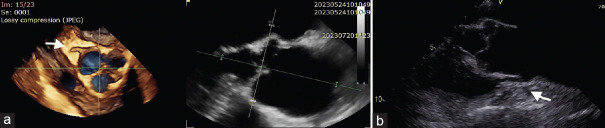

This case report presents a rare scenario involving a congenital anomaly of the right coronary artery's (RCA) origin in association with an ascending aortic aneurysm. While both anomalies are individually recognized in the literature, their coexistence and potential interplay remain understudied. The aim of this report is to emphasize the challenges and implications associated with such a combination. A 78-year-old male patient with an enlarged ascending aortic aneurysm necessitating surgical intervention was found to have an anomalous origin of the RCA during preoperative coronary angiography, confirmed by computed tomography scan. Transesophageal echocardiography further elucidated the coronary abnormality. Intraoperatively, successful aortic replacement was performed, and careful repositioning of the anomalous right coronary ostium was achieved. This case raises important considerations regarding the potential complications arising from coronary anomalies and their impact on the surgical management of ascending aortic aneurysms. The rarity of this combination limits our understanding of their association, making a multidisciplinary approach crucial for optimal patient care. Further research and comprehensive evaluation of similar cases are necessary to better understand the relationship between coronary anomalies and ascending aortic aneurysms. Such investigations will help in improving treatment strategies and outcomes for patients with these complex conditions.